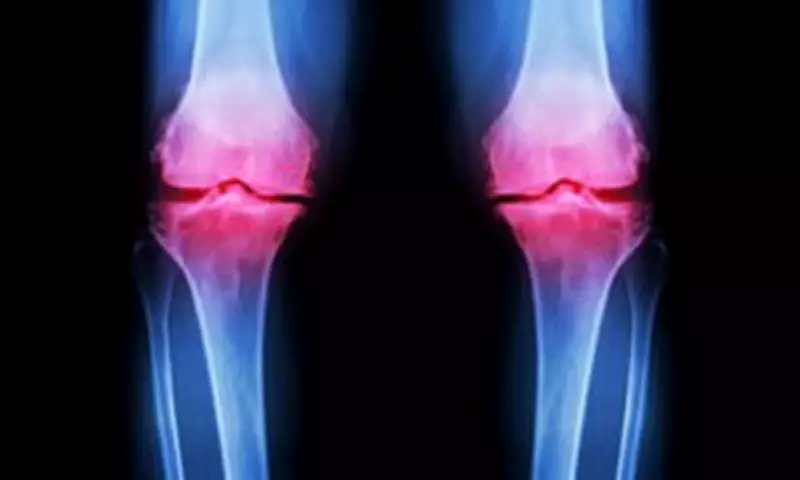

Osteoarthritis affects approximately 10 million people in the UK and is the most common form of arthritis. Typically developing from around age 45, it involves the breakdown of protective cartilage on bone ends, preventing joints from fully repairing themselves. Factors contributing to cartilage degradation include genetics, obesity, repeated joint stress, age, smoking, and injury.

Post-traumatic osteoarthritis is specifically related to fractures extending into joints like the ankle, wrist, and knee, which can cause improper healing and accelerate cartilage breakdown. By age 70, about half of people develop arthritis, but diagnoses are now occurring much earlier in life.